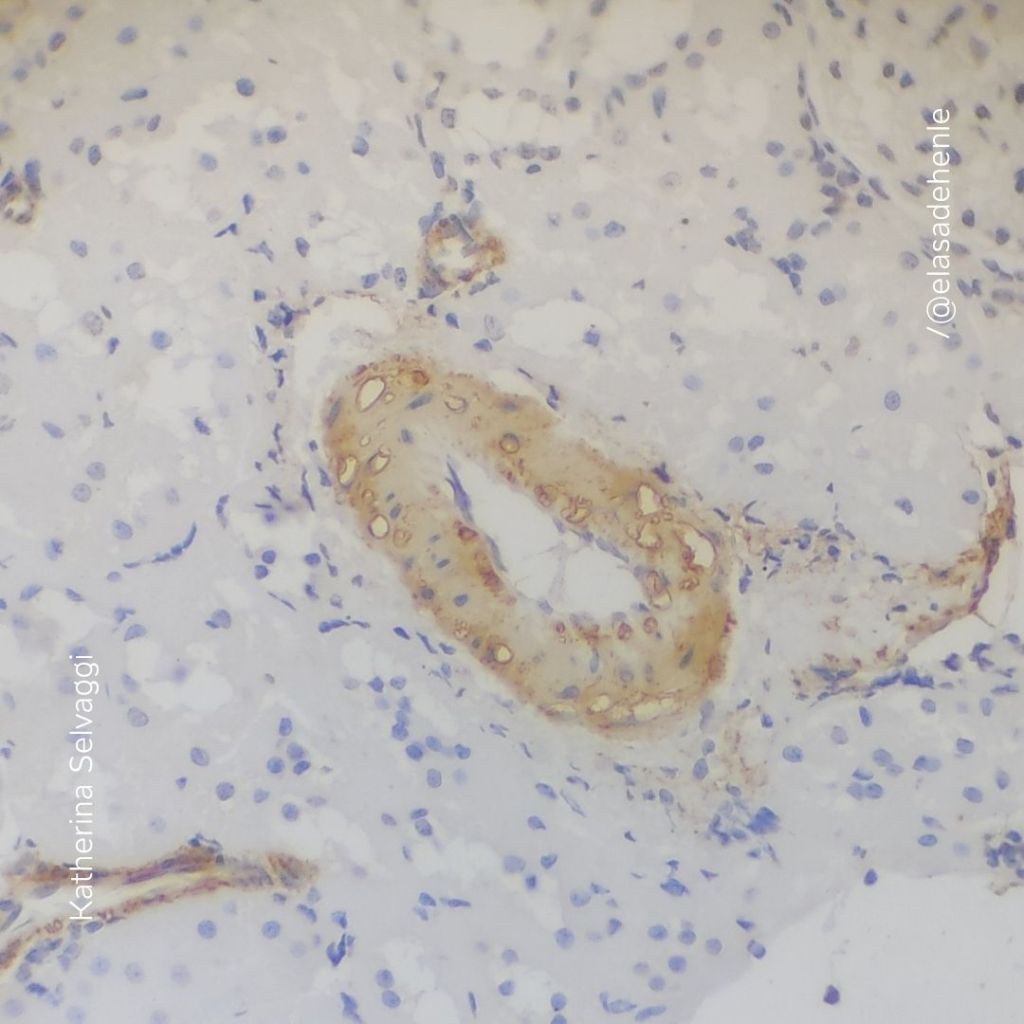

Inmunohistoquímica

Riñón. SMA.

Hospital de Clínicas